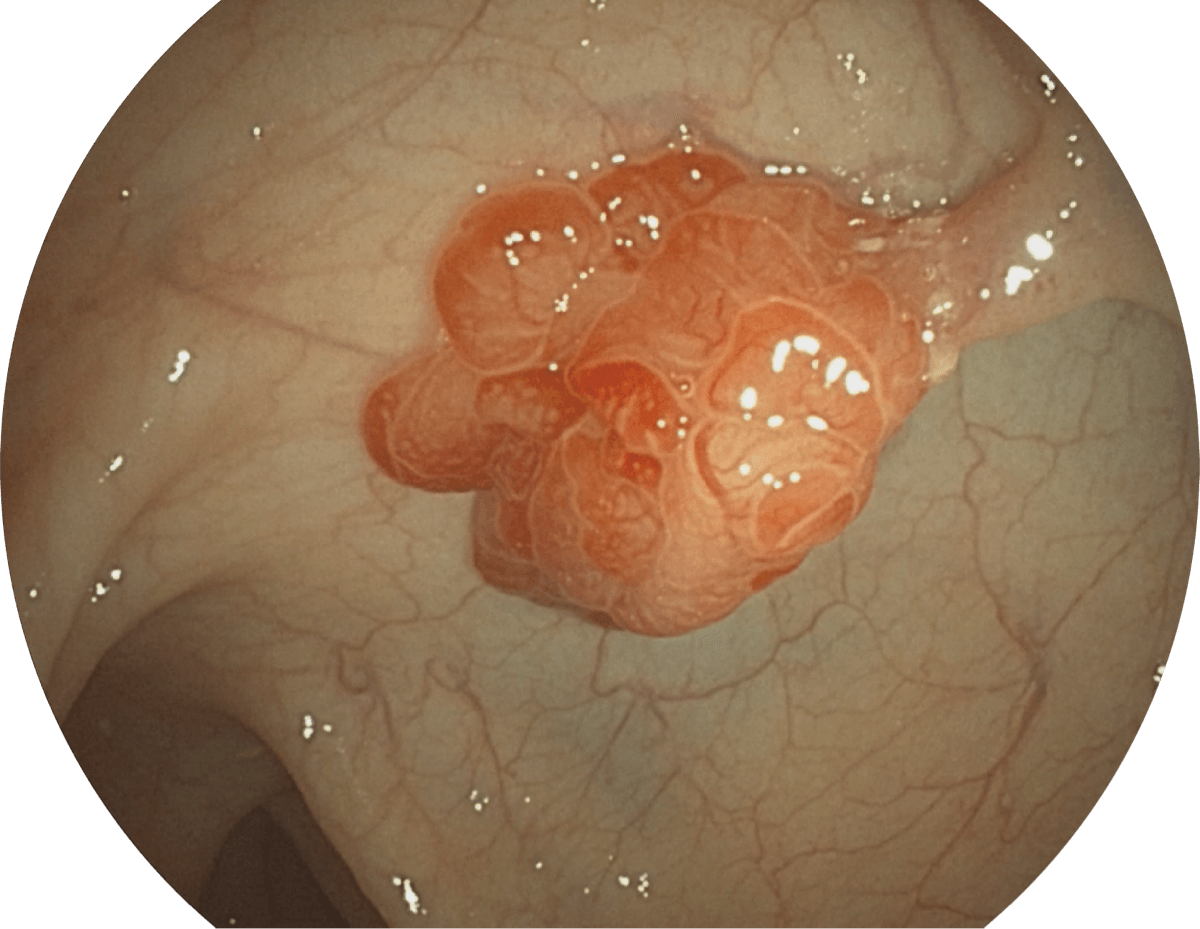

具有聚谱成像技术(SFI)及光电复合染色成像技术(VIST),可完美呈现粘膜细节及病变特征。

WL

SFI

VIST